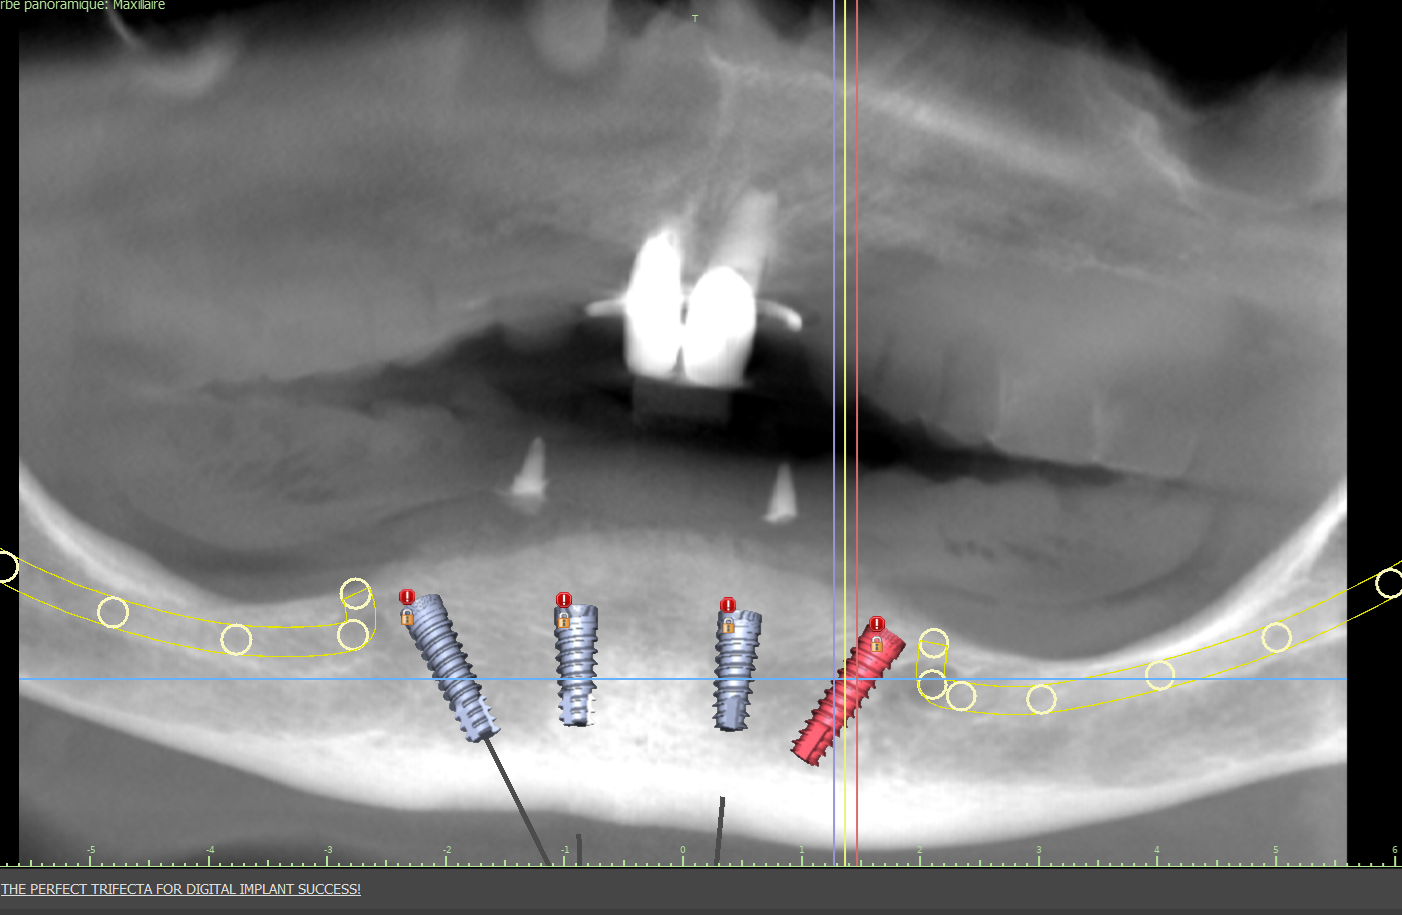

Réhabilitation complète avec mise en charge immédiate (4 implants bas / 6 implants haut)

Le patient se présente avec des dents qui bougent, en haut et en bas.

Nous avons commencé par la mâchoire inférieure avec 4 implants et une mise en charge immédiate.

Trois mois après, le haut a été fait avec le même principe avec 6 implants.

Cette fois-ci, il existait un déficit osseux, résolu par une technique d’expansion sans avoir recours à la greffe d’os.

Les prothèses réalisées sont vissées, ce qui permet de les enlever, les nettoyer une fois par an, ou résoudre n’importe quel problème.